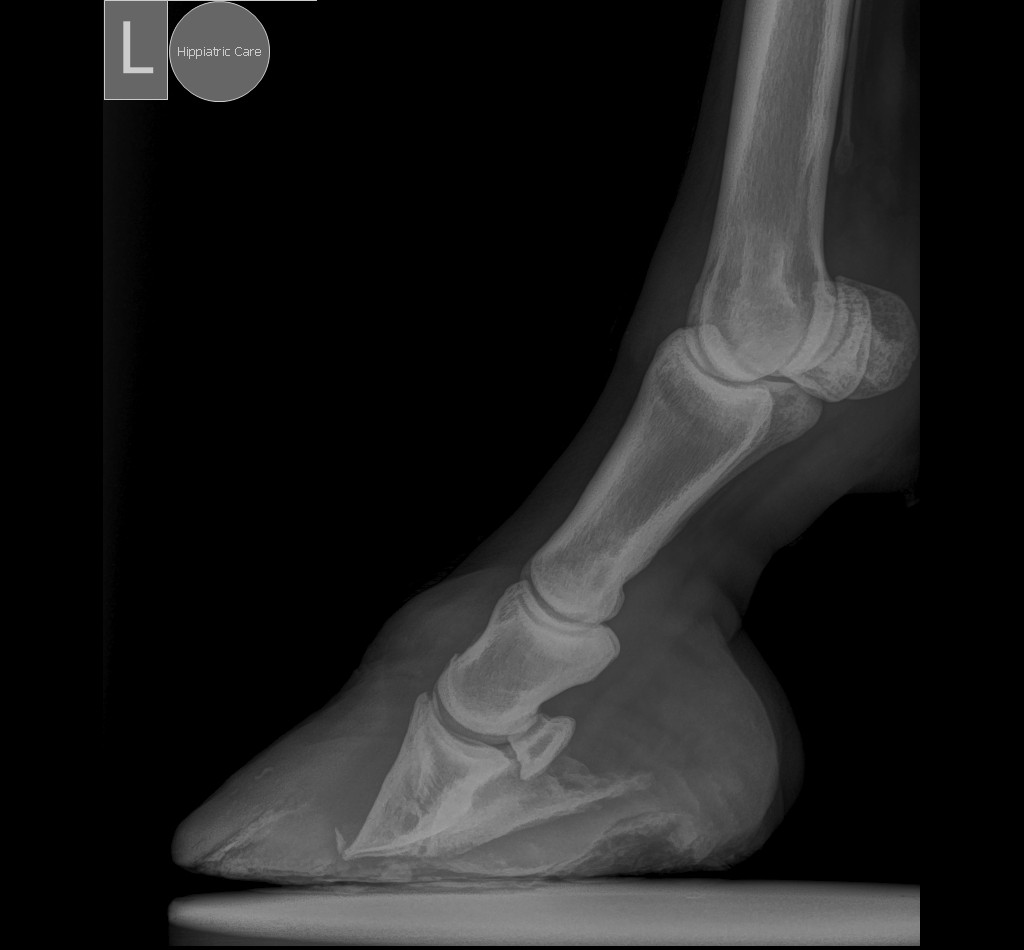

Ο ακτινογραφικός έλεγχος είναι απαραίτητος για:

✓ Την επιβεβαίωση της διάγνωσης.

✓ Τον καθορισμό του βαθμού και του τύπου μετατόπισης της 3ης φάλαγγας.

✓ Την καθοδήγηση για το λιμάρισμα της οπλής και το πετάλωμα.

✓ Την αξιολόγηση της πορείας της νόσου και της ανταπόκρισης στη θεραπεία.

Η φλεβογραφία αποτελεί ένα ιδιαίτερα χρήσιμο εργαλείο για τη διάγνωση και θεραπεία της ενδονυχίτιδας, καθώς επιτρέπει την εκτίμηση της αγγειακής βλάβης εντός της οπλής πριν από την εμφάνιση αλλοιώσεων στις συμβατικές ακτινογραφίες. Η αξία της είναι μεγαλύτερη όταν εφαρμόζεται κατά την έναρξη της νόσου, διότι αποκαλύπτει τον βαθμό της ήδη εγκατεστημένης αγγειακής βλάβης και συμβάλλει στον καθορισμό της κατάλληλης θεραπευτικής στρατηγικής.

Το σωστό λιμάρισμα και το πετάλωμα πρέπει να καθοδηγούνται ακτινογραφικά και να προσαρμόζονται στις ανάγκες κάθε αλόγου ξεχωριστά.